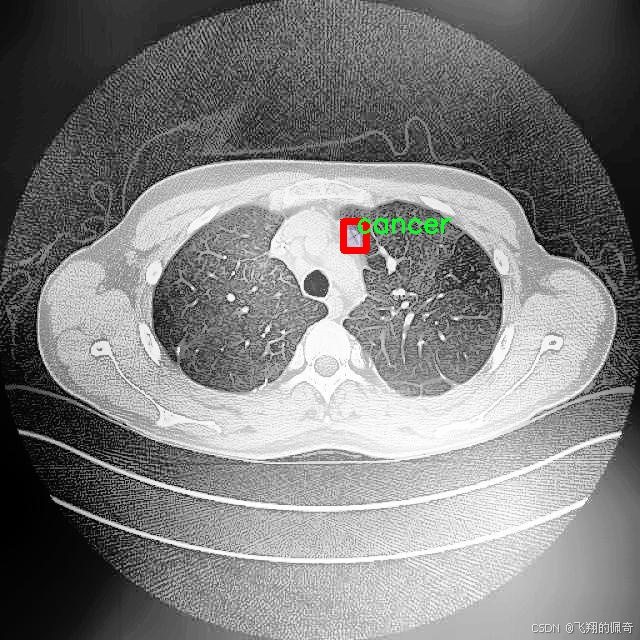

本研究将基于改进的YOLOv8模型,构建一个高效的肺结节图像分割系统。所使用的数据集包含1600幅图像,涵盖了三类重要的病理类型:腺癌、癌症和结节。这些数据不仅为模型的训练提供了丰富的样本,也为后续的模型评估和验证奠定了基础。通过对不同类别的肺结节进行精确分割,研究旨在提高模型在实际应用中的鲁棒性和准确性,进而为临床医生提供更为可靠的辅助诊断工具。

图片效果

在肺结节图像分割的研究中,数据集的选择与构建至关重要。本研究所采用的数据集名为“Lung Nodule Segmentation study”,其设计旨在为改进YOLOv8-seg模型提供高质量的训练数据。该数据集专注于肺部影像中的结节分割,特别是针对不同类型的肺结节进行精确标注,以便于后续的深度学习模型训练和性能评估。

“Lung Nodule Segmentation study”数据集中包含三种主要类别,分别为腺癌(adenocarcinoma)、癌症(cancer)和结节(nodule)。这些类别的选择不仅反映了肺部影像学中的常见病理类型,也为模型的多样性和适应性提供了基础。腺癌作为一种常见的肺癌类型,其在影像学上的表现与其他类型的肺结节有显著差异,因此在数据集中占据了重要地位。癌症这一类别则涵盖了更广泛的病理变化,旨在提高模型对不同癌症类型的识别能力。结节类别则是数据集的核心,主要用于训练模型在图像中准确识别和分割出肺结节的区域。